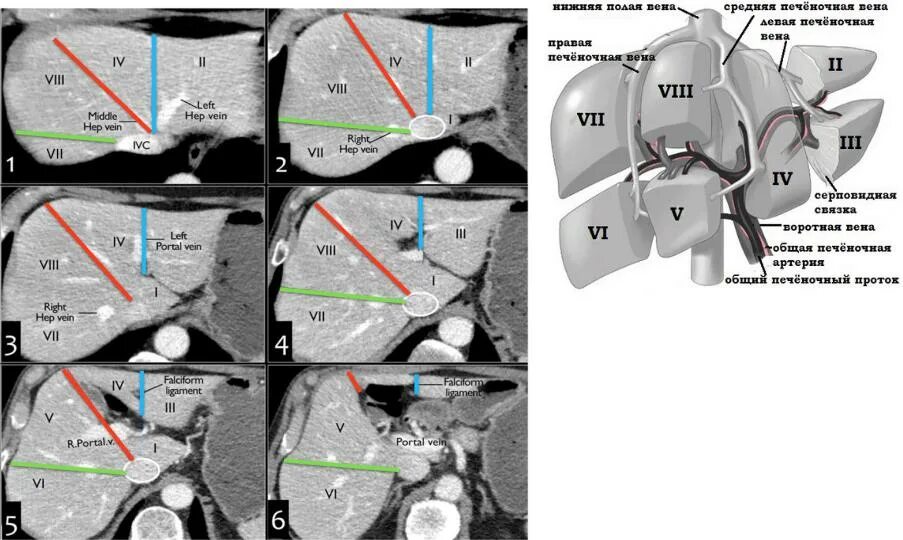

6 7 сегмент печени